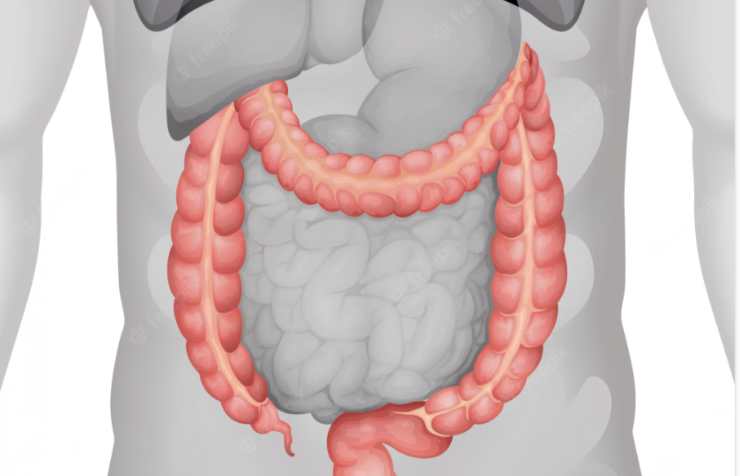

La diverticolite è la presenza di estroflessioni della mucosa di tubo digerente, pareti intestinali o colon. Cosa si deve evitare di mangiare?

Partiamo però dal capire cos’è questa patologia dell’apparato digerente, come si manifesta e come si cura. Di fatto queste estroflessioni, di cui abbiamo già parlato, sono come delle piccole tasche che si presentano e possono portare a diversi sintomi. Intanto va specificato, che come la maggior parte delle malattie, anche questa presenta sintomi diversi in base all’organismo. In molti presenta febbre e nausea per portare in alcuni casi alla diarrea e in altri alla stitichezza oltre al sangue nelle feci.

La parte maggiormente colpita, il 95% dei pazienti la vedono attaccata, è il sigma. La diverticolite si scopre quando nell’analisi del sangue troviamo dei valori decisamente più alti di proteina C reattiva. La febbre alta va e viene e porta dei brividi, ma ha sempre le caratteristiche di una febbre settica e questo per l’origine della patologia. Attenzione poi alla perforazione perché la diverticolite può portare alla rottura di una parete intestinale e questo porta a gravissime complicazioni, tra cui la peritonite e cioè il riempimento della cavità peritoneale di batteri che può portare anche alla morte.